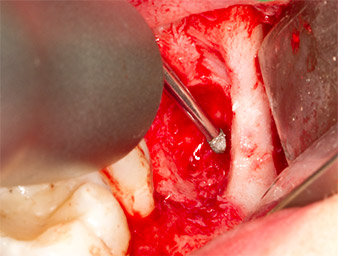

To obtain autogenous material for subsequent wound treatment, healthy bone chips were harvested from the surroundings of the root remnant with a piezo surgical instrument (Piezomed B5) (Fig. 5).

Piezomed B5

Fig. 5: Bone in the region of the alveole is lifted with a chisel-shaped piezo surgical instrument (Piezomed B5). This bone is used as autologous augmentation material after removal of the root remnant (cf. Fig. 13 and 14).

The autogenous tissue was removed with the scraper-shaped section of the working part of the instrument and stored in a physiological saline solution until further use (cf. Fig. 13).